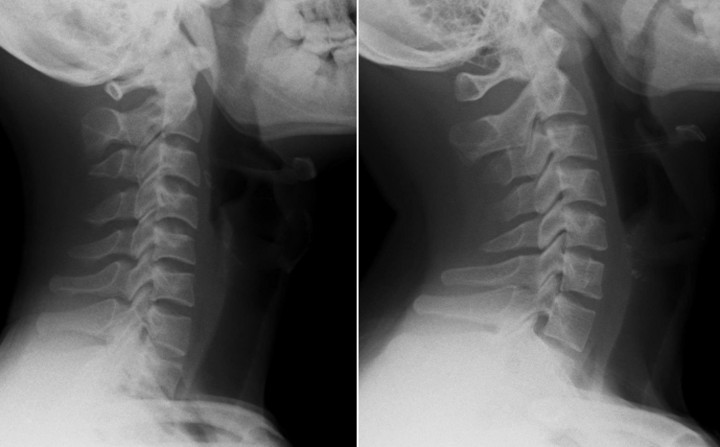

Kết quả chụp X-quang cho thấy cột sống cổ của bệnh nhân mất độ cong sinh lý, khiến các đốt sống cổ gần như xếp dọc thay vì có độ ưỡn ra trước như bình thường.

Cột sống cổ của nam thanh niên thẳng đứng (ảnh 1) và cột sống cổ bình thường (ảnh 2). (Ảnh: BSCC)

Tiến sĩ, bác sĩ Ngô Thị Kim Oanh - Phó Trưởng khoa Châm cứu - Dưỡng sinh, Bệnh viện Đại học Y Dược TP HCM - Cơ sở 3 cho biết, ở người trưởng thành khỏe mạnh, cột sống cổ có độ cong nhẹ về phía trước - gọi là độ ưỡn sinh lý giúp phân bổ đều lực từ đầu xuống vai và thân trên, hấp thu lực chấn động từ các hoạt động thường ngày (đi, đứng, chạy...), giảm tải trọng lên đĩa đệm và khớp liên đốt sống.

Khi đường cong này bị mất, cột sống trở nên “thẳng như cây gậy” làm tăng áp lực lên các đĩa đệm, khớp, dây chằng và cơ quanh cổ. Về lâu dài, điều đó có thể dẫn đến thoái hóa sớm, thoát vị đĩa đệm cổ, chèn ép rễ thần kinh hoặc tủy sống, gây ra các triệu chứng như đau, tê tay, chóng mặt, thậm chí yếu cơ.